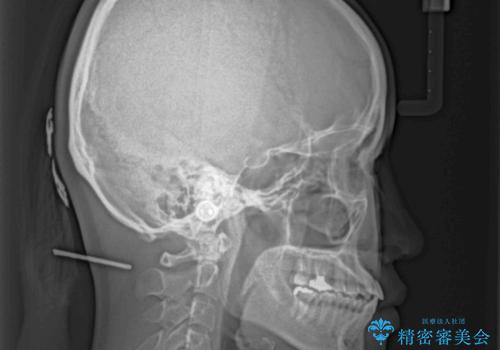

骨格的に下顎が前方に位置していましたが、歯列矯正で改善できると判断し、ワイヤー装置にて矯正治療を行うこととしました。

このような咬み合わせの方の多くは、舌の突出癖が強い傾向にあり、反対咬合改善後に開咬となってしまい、なかなか治療が終わらないことがあります。

こちらの患者様は、舌のトレーニングを治療開始前から徹底的に実践していただき、僅か8ヶ月という短期間で治療を終えることができました。